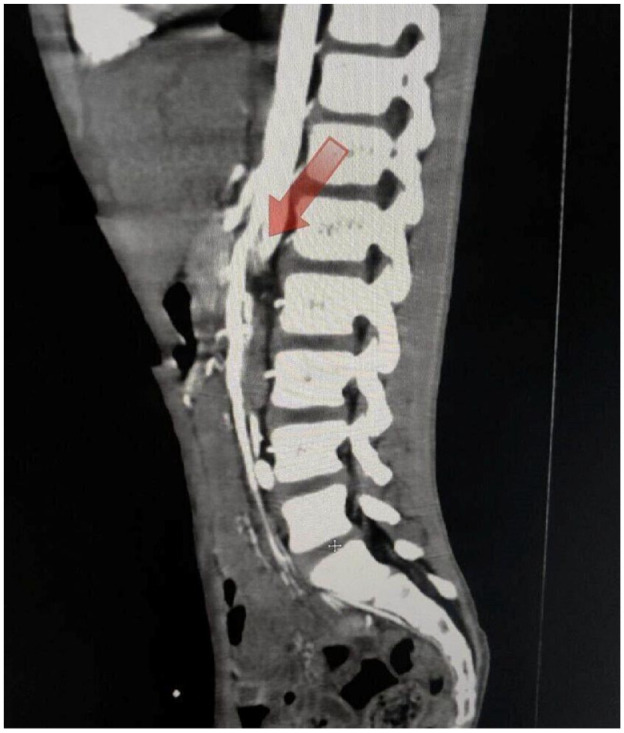

肠系膜上动脉综合征(SMAS)是一种因肠系膜上动脉压迫十二指肠而引起的罕见病症,但有可能危及生命。我们报告了一例 11 岁男性病例,他主诉腹痛和间歇性呕吐已持续 3 周。在放射学检查结果的帮助下,确诊为 SMAS。患者接受了营养支持、促动力药和胃减压等保守治疗。治疗两周后,患者的症状有所改善,康复出院。

Superior Mesenteric Artery Syndrome (SMAS) is a rare but potentially life-threatening condition caused by the compression of the duodenum by the superior mesenteric artery. We report a case of an 11-year-old male who complaint of abdominal pain and intermittent vomiting for last 3 weeks. Diagnosis of SMAS was made with the help of radiological findings. The patient was managed conservatively with nutritional support, prokinetic agents, and stomach decompression. After 2 weeks of treatment, the patient's symptoms improved, and he was discharged from the hospital.